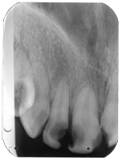

Radiografii retroalveolare la inceputul si la sfīrsitul tratamentului endodontic